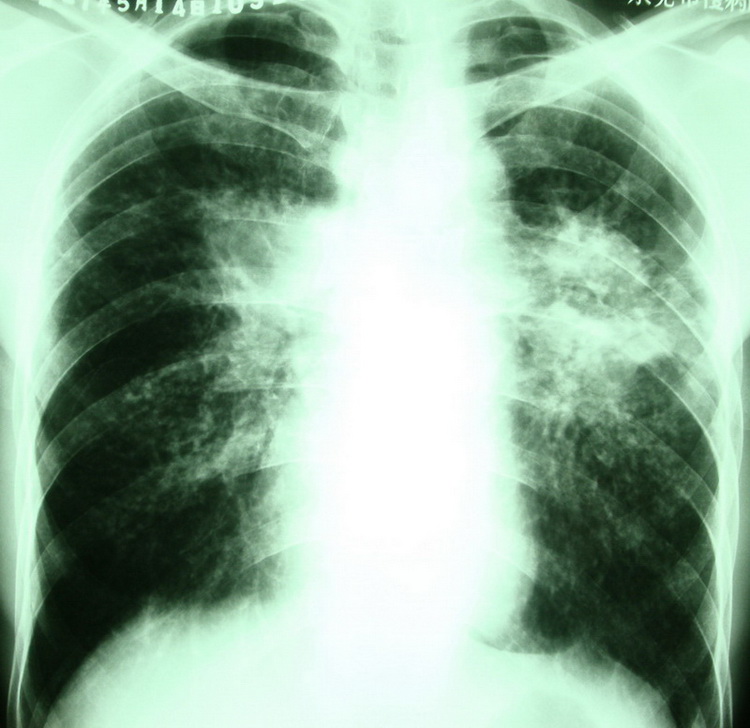

按顺序依次是:(都有粉尘职业史)

何某,男,34岁,i尘肺,右上肺结核?